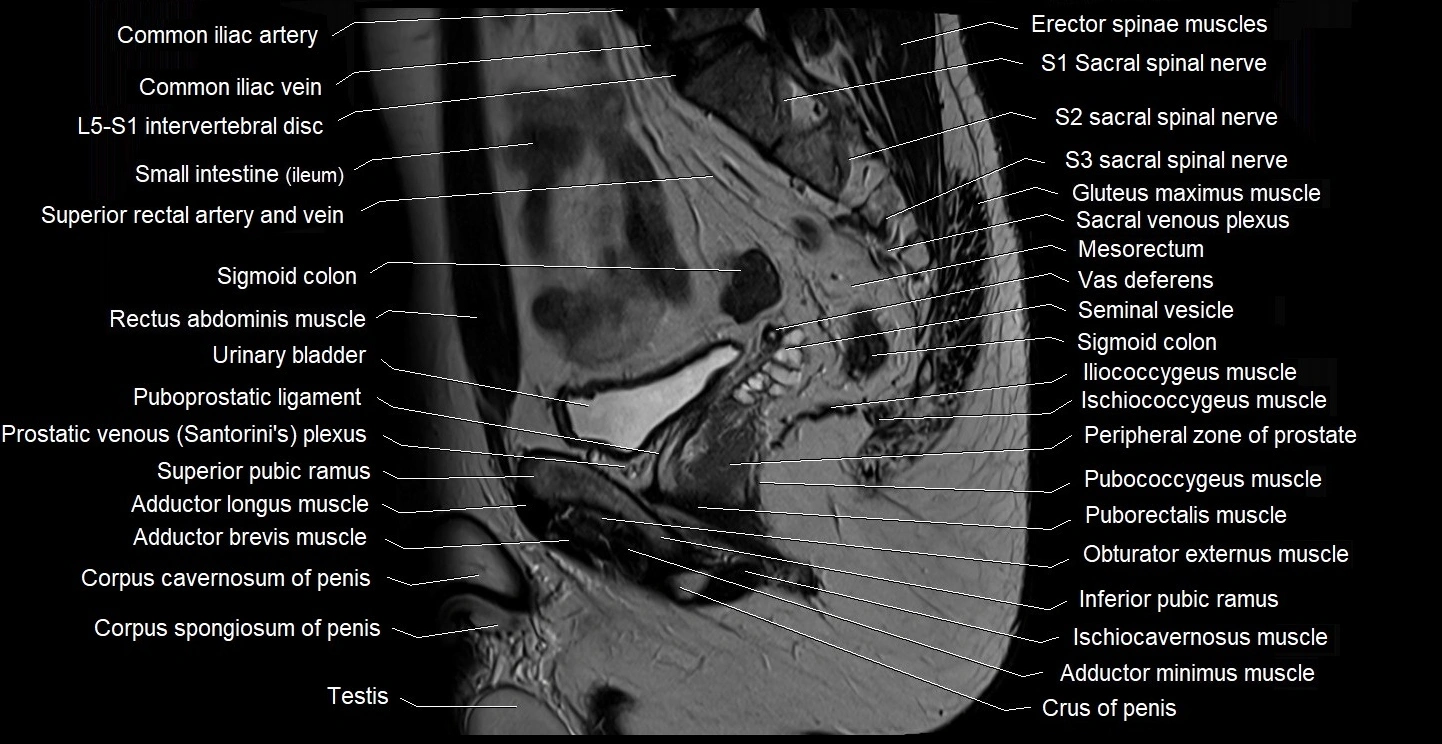

- Common iliac vein

- Corpus spongiosum

- Crus of penis

- Erector spinae muscles

- Gluteus maximus muscle

- Iliococcygeus muscle

- Ischiococcygeus muscle

- L5–S1 Intervertebral disc

- Mesorectum

- Peripheral zone of prostate

- Pubococcygeus muscle

- Puboprostatic ligament

- Puborectalis muscle

- Seminal vesicle

- Sigmoid colon

- Small intestine

- Superior rectal artery

- Testis

- Transitional zone of prostate

- Vas deferens